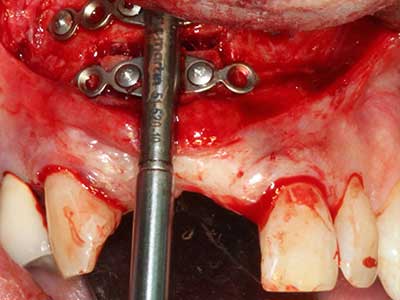

Quando le procedure chirurgiche vengono eseguite sull'osso nelle immediate vicinanze di strutture sensibili, come vasi sanguigni o nervi, gli strumenti rotanti pongono un rischio significativo di lesione iatrogena. I dispositivi piezoelettrici possono essere utili per la preparazione delle coperture ossee e la rimozione del tessuto duro in prossimità dei nervi, in particolare per la loro esposizione dopo una lesione iatrogena, ma anche durante la lateralizzazione dei nervi per le procedure di resezione e ricostruzione o il posizionamento di impianti (figg. 17-20). Il contatto leggero tra puntina piezoelettrica e nervo non causa generalmente danni, ma se si procede senza prestare attenzione con movimenti a sega o raccordi con residui di substrati ossei possono verificarsi danni al nervo temporanei o anche permanenti. Il rischio di danno, tuttavia, è considerato sostanzialmente inferiore al rischio presente utilizzando seghe o frese (Pereira, Gealh et al. 2014).